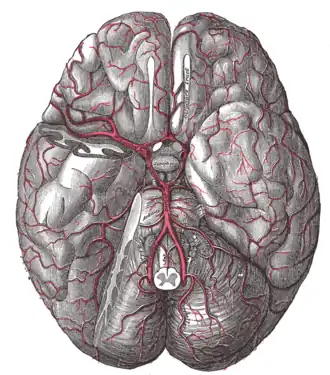

The brain and the arteries of the base of the brain, viewed from below, with the front of the brain at the top of the image. The temporal pole of the cerebrum and a portion of the cerebellar hemisphere have been removed on the right side. | |

In human anatomy, the left and right posterior communicating arteries are small[1]: 471 arteries at the base of the brain that form part of the circle of Willis.

Each posterior communicating artery is situated within the interpeduncular cistern, superolateral to the pituitary gland.[2]: 450 Each are is situated upon the medial surface of the ipsilateral cerebral peduncle[1]: 477 and adjacent to the anterior perforated substance.[1]: 471